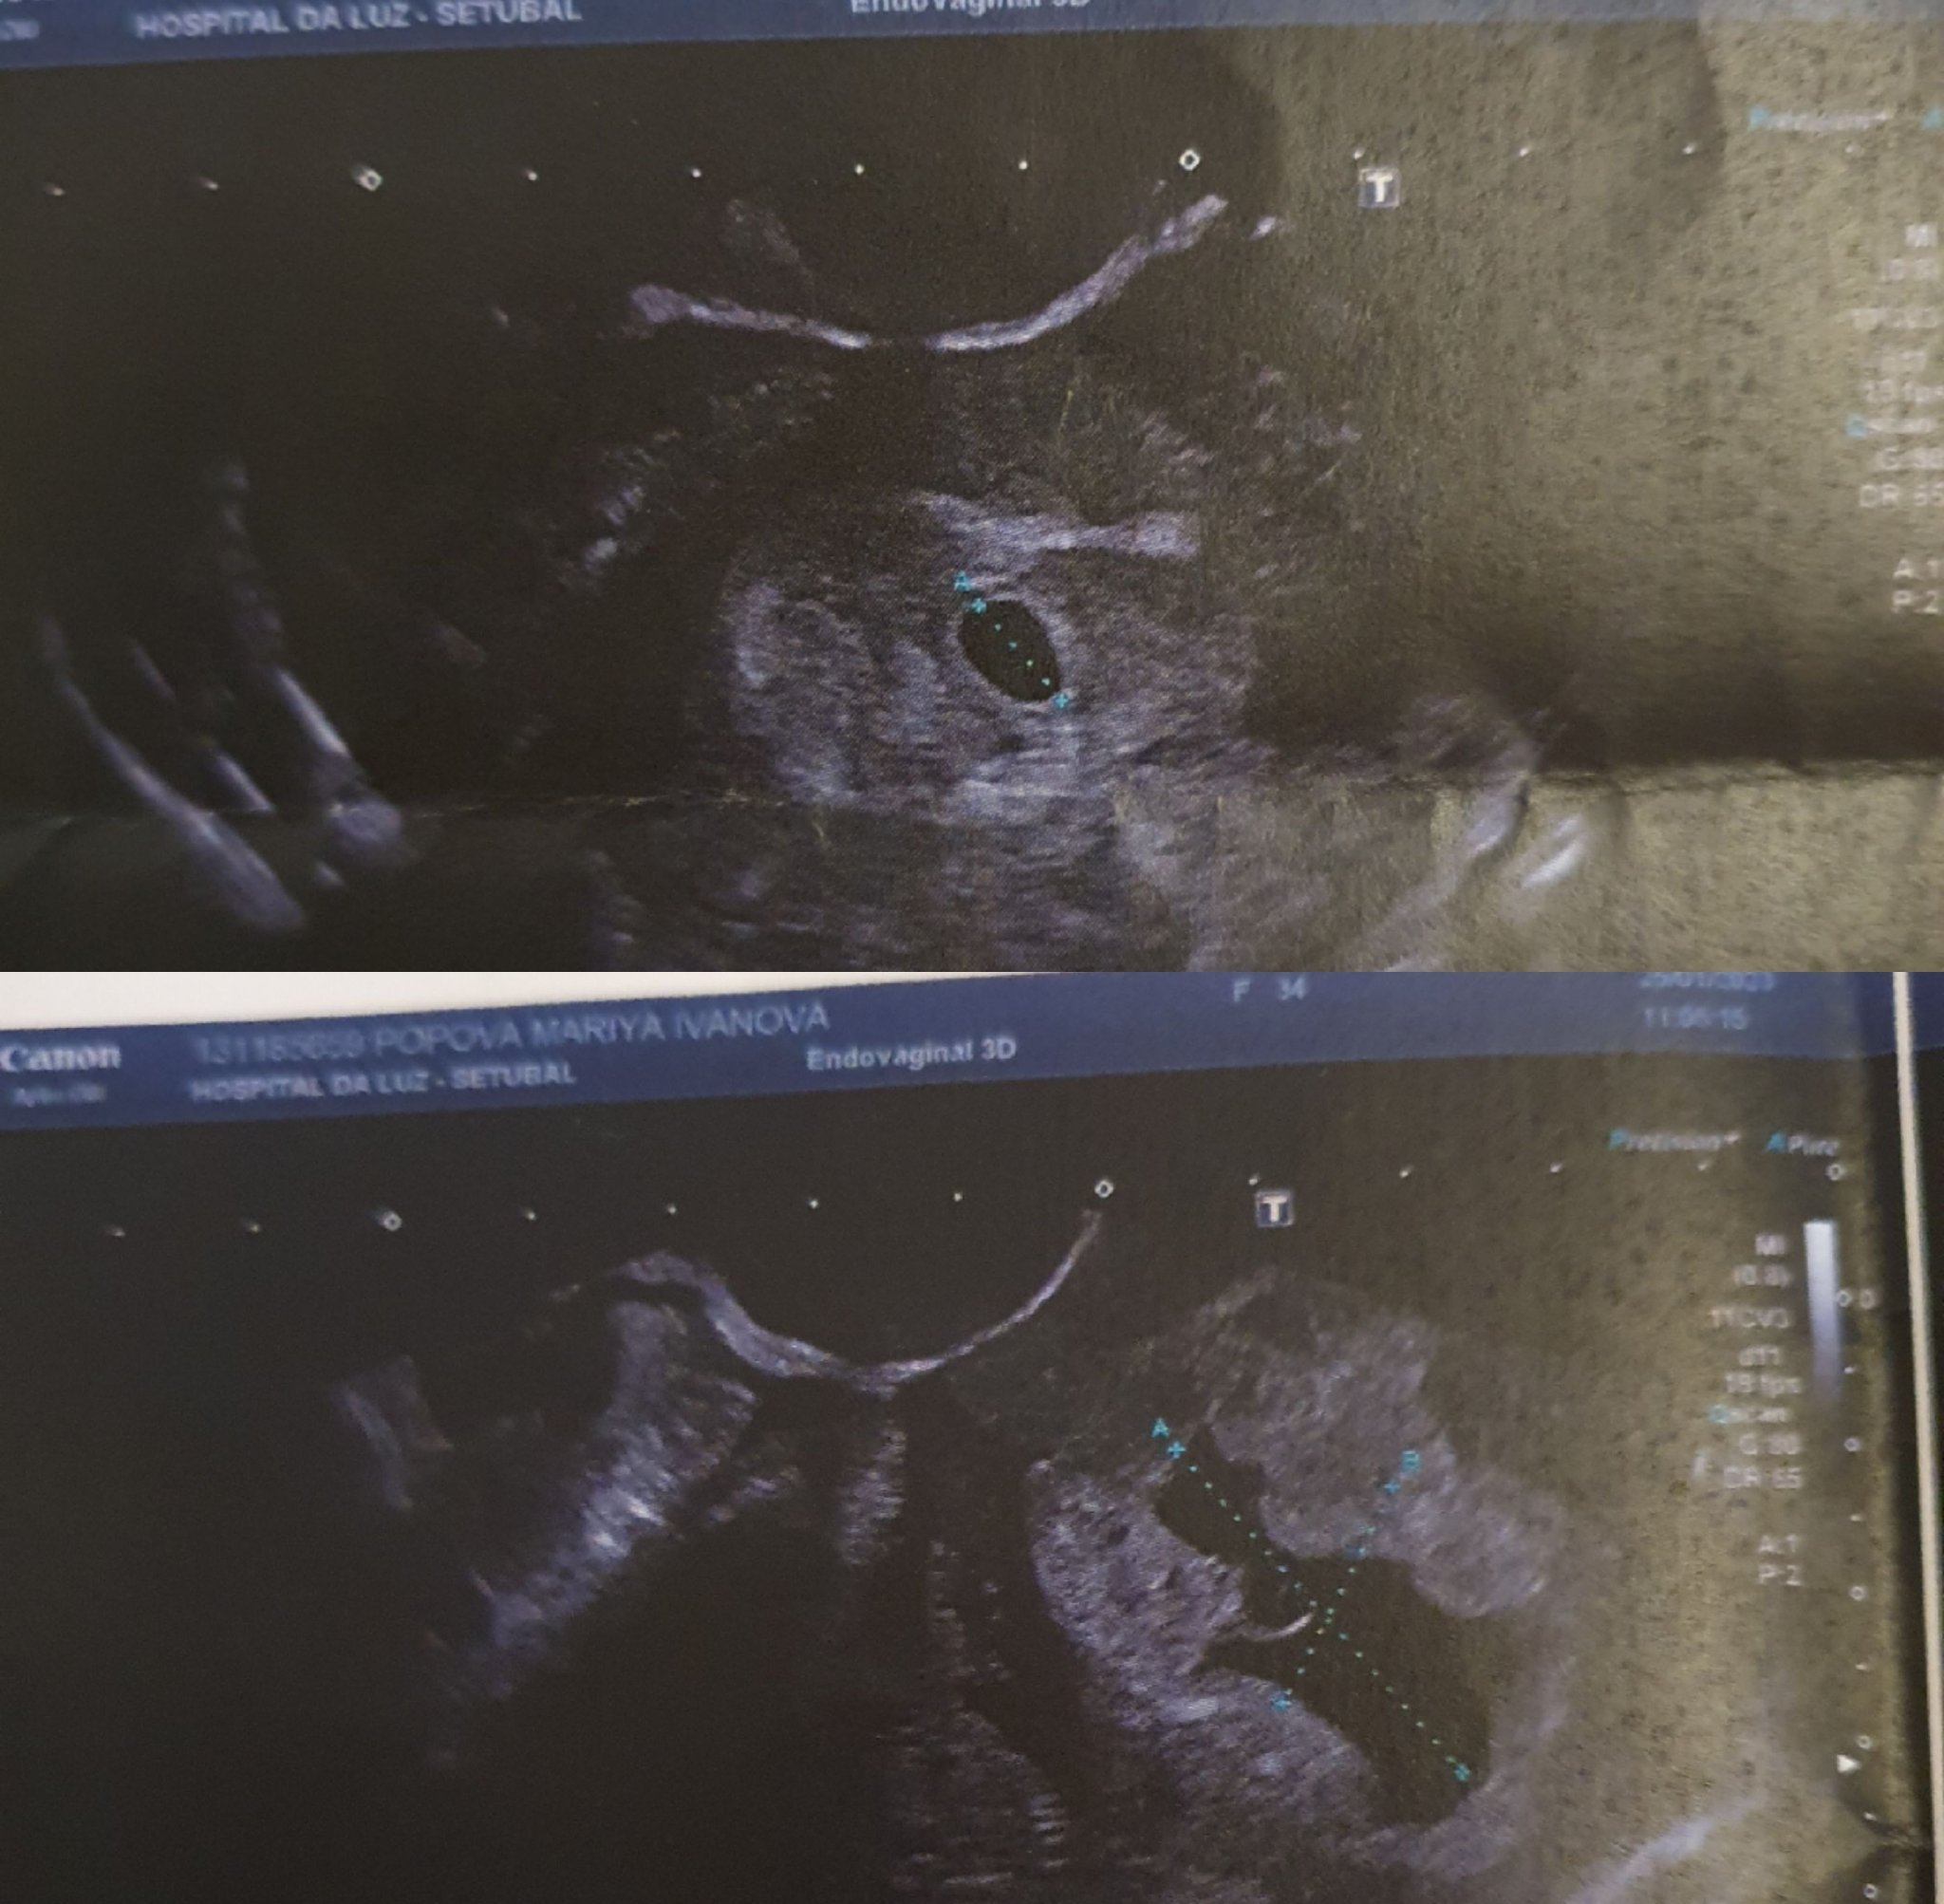

Мнение - на втората снимка се вижда безформената тъмна част. Ако това наистина е сак не мисля, че има шанс.